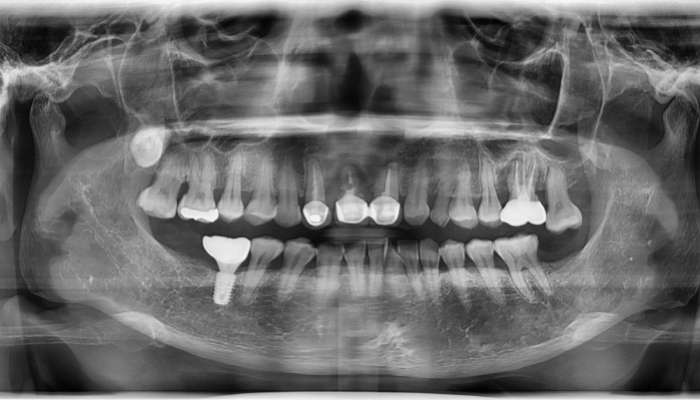

상악동거상술 수술사진

상악동거상술 전후 사례

• 식립 전

식립 후

• 식립전

식립후